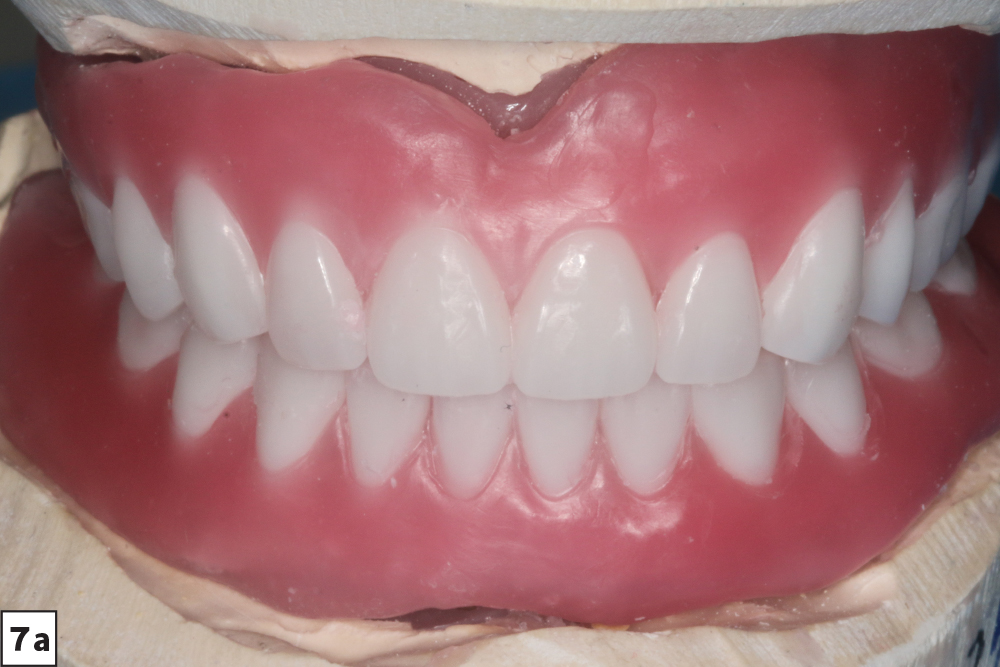

The following case report illustrates a straightforward clinical workflow for delivering a Locator® Overdenture (Glidewell; Newport Beach, Calif.) — a removable appliance that seats over Locator Abutments connected to the implants. Denture caps are embedded in the overdenture and provide retention by seating over and engaging the Locator Abutments. By stabilizing the prosthesis, these retentive devices improve function and chewing efficiency.

Our patient is a middle-aged female who presented with a chief complaint of ill-fitting, unstable maxillary and mandibular conventional dentures. We discussed several options, including relining her existing dentures, fabrication of new conventional dentures, implant-retained overdentures and fixed implant-supported prostheses. The patient opted for implant placement and restoration with a Locator Overdenture — which would provide an effective, economical means of addressing the patient’s needs and improving prosthetic stability and dental function.